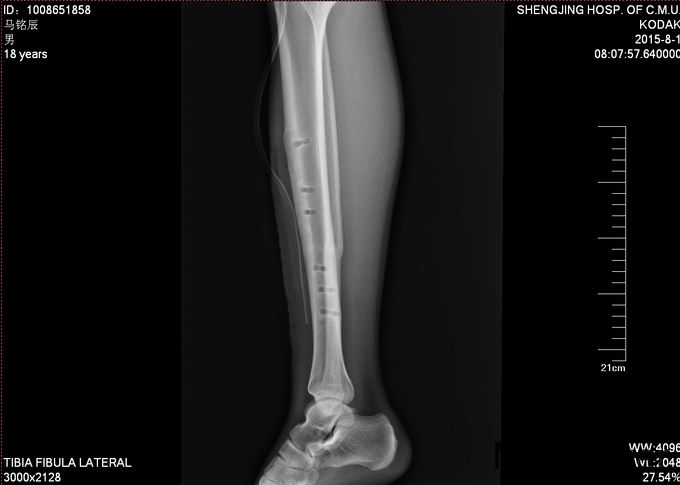

现病史:患者及家属自诉于2013年11月9日下午2点因打篮球摔伤致右小腿疼痛、肿胀,后于2013年11月11号于我院行胫腓骨骨折切开复位内固定术,现内固定物固定已一年半来我科继续治疗。病来无发烧发热,无咳嗽,无其他不良主诉,饮食二便正常,体重近期无明显变化。

患者入病房,右小腿处可见一约10cm瘢痕,瘢痕部无明显压痛,右下肢无轴向叩击痛,无明显肿胀,足趾背伸跖屈肌力5级,足背部及小腿感觉正常,双下肢等长。足背动脉可触及搏动。其余肢体未见异

入院后完善检查,及功能检查后,于全麻下行右胫腓骨骨折术后内固定物出去术,术后第二天换药示切口无红肿渗出,患者自动退院。